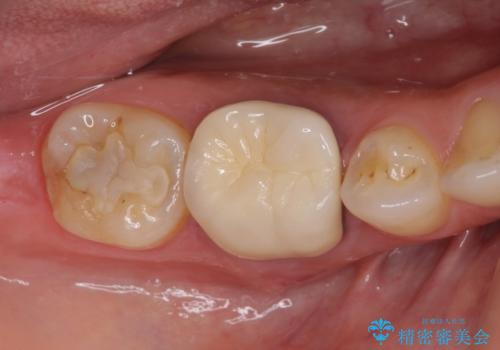

奥歯の深い虫歯をオールセラミックで治療